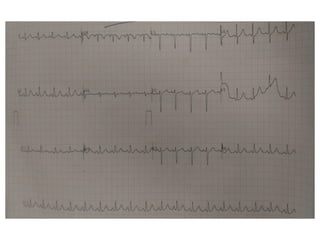

• This form of VT is associated with a

characteristic ECG morphology

Wide complex tachycardia

LBBB

inferior axis suggesting origin from the right

ventricle outflow tract .

• A QS pattern in lead avR and monophasic R

waves in leads II, III, avF and V6.